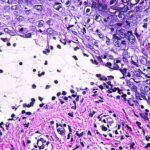

intensity of epidermal necrosis varies from vacuolated individual keratinocytes surrounded by lymphocytes (satellite cell necrosis) at the basal unit to confluent necrosis in association with intraepidermal and subepidermal vesicles. The dermal infiltrate comprises lymphocytes and histiocytes. Eosinophils may also be present. Although one study has noted a significant number of eosinophils in drug-induced EM, this has not been noted by others. In the authors’ estimation, a generous number of eosinophils exclude EM. One study has found that an acrosyringium concentration of apoptotic keratinocytes in EM is a clue to a drug etiology . In early lesions of SJSITEN, apoptotic keratinocytes are observed scattered in the basal layer of the epidermis. In established lesions, there are numerous necrotic keratinocytes, even full-thickness epidermal necrosis, and a subepidermal bulla. The dermal inflammatory infiltrate is sparser in TEN than in EM (Fig. 9-278). Extravasated erythrocytes are commonly found within the blister cavity. Melanophages within the papillary dermis occur in late lesions. Eccrine epithelium shows a variety of changes from basal cell apoptosis to necrosis of the duct. |

In general, EM shows less epidermal necrosis, more dermal inflammation, and exocytosis, whereas SJS and TEN reveal more epidermal necrosis, less dermal inflammation, and exocytosis. However, due to the overlapping histologic features among EM, SJS, and TEN, histologic examination-while important for recognizing the spectrum of disorders-is not reliable for classifying the disease. Correlation with clinical presentation is essential. |